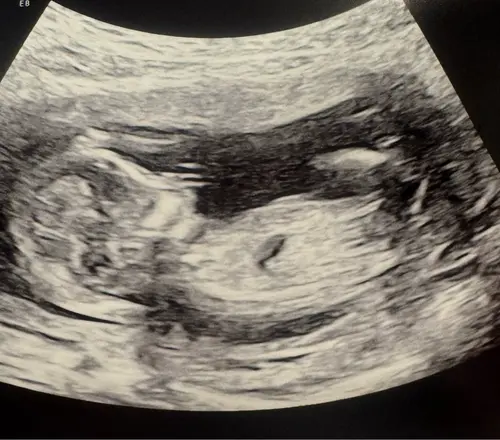

Is hier iets op te zien? 13.0 precies.

Meisje